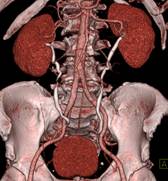

头颅一站式检查:320排容积CT覆盖范围达16cm,球管旋转一周可以覆盖整个脑组织,获得全脑0.5mm层厚各向同性全脑信息。一次扫描可以获得平扫容积图像、以时间为序列全脑动态3D-CTA图像(包括纯动、静脉期成像)及全脑灌注图像。一次检查即可排除脑出血、动脉瘤、动脉狭窄、梗塞、脑实质供血异常等多种病变及进行脑卒中筛查。

脑血管畸形CTA ,大血管成像:动态容积成像实现大范围动态血管检查